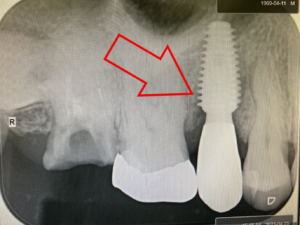

インプラント治療前と後のレントゲン写真です。

こちらが治療前のレントゲン写真です。丸を付けた箇所がインプラント治療を受ける場所です。

左の赤丸は、虫歯の為、歯の根っこが悪くなり抜歯が必要な場所です。(右上4番)

①虫歯の為抜歯が必要であった歯(右上の前から4番目の歯)の抜歯を行い(上の写真)

②そして、抜いた箇所にそのままインプラントを埋入(抜歯即時インプラント)

③インプラントを埋入後、仮歯を装着して終了です。